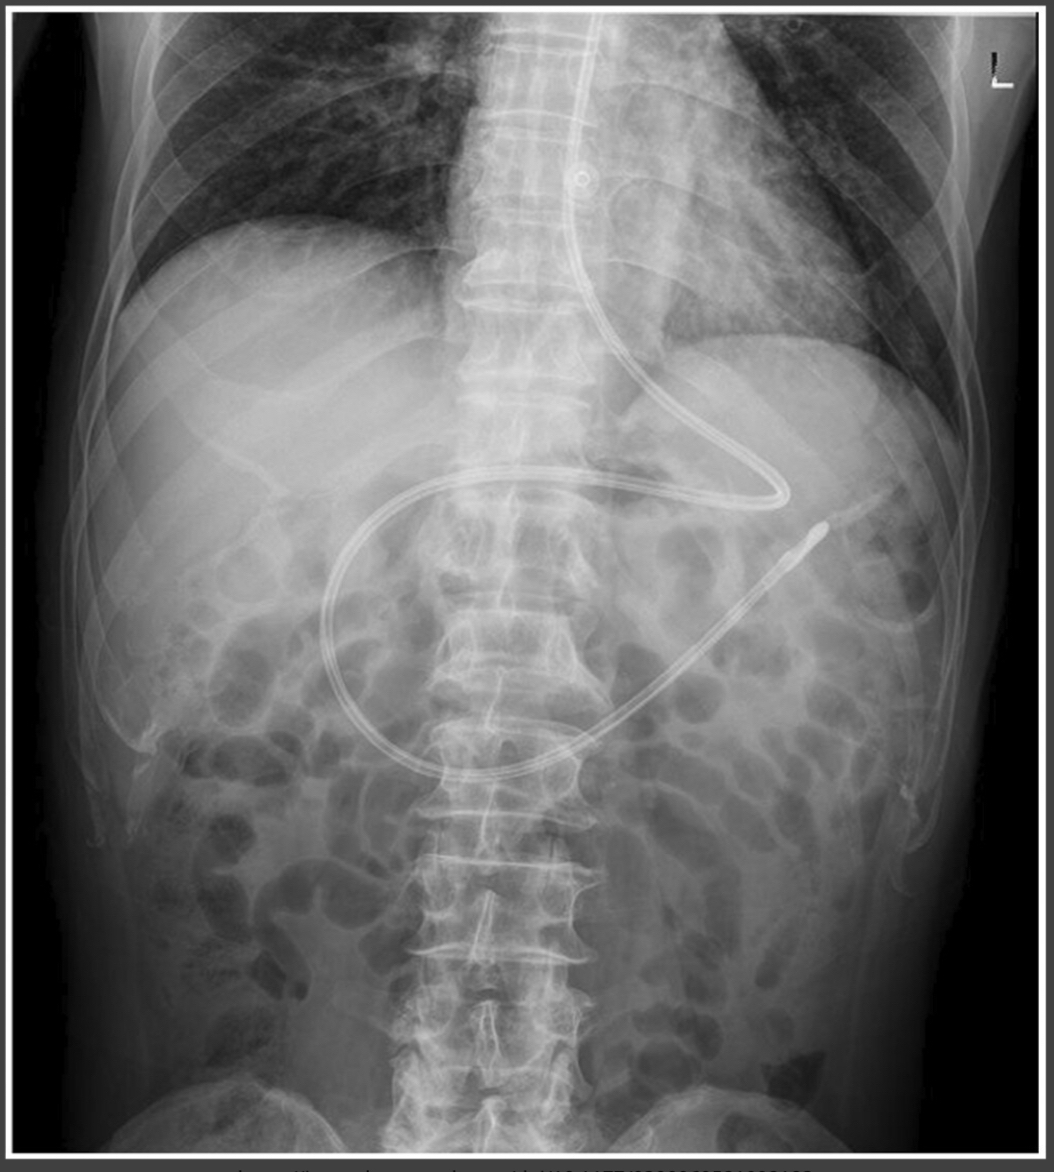

Nasogastric (NG) Tube

Tip should be below diaphragm.

Tip remains left of spine.

Nasoduodenal Tube

Crosses from left to right side of spine.

Advances toward jejunum.

Small Bowel Obstruction

“Stacked coin” appearance.

Air-fluid levels visible on erect film.

Dilated Bowel

Indicates large bowel obstruction.